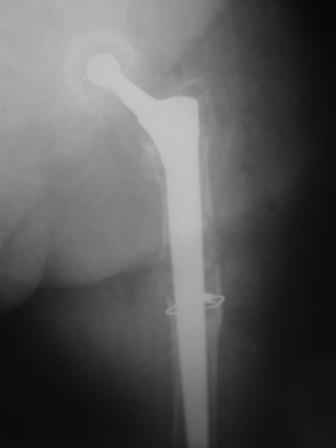

Reminded me of a case I did a couple years ago - 30 year old woman with juvenile rheumatoid arthritis and a nonunion below her stem. Fixed with retrograde nail which docked with the stem and a lateral locking plate. Image attached. One of the companies should come up with a stem design and nail system that anticipates this need.